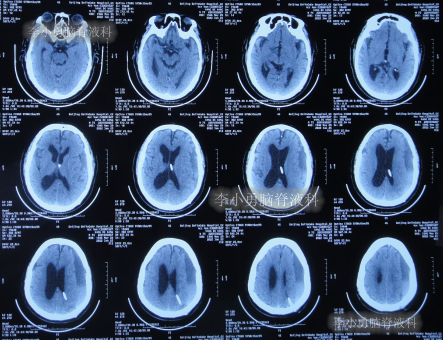

发现脑积水后8天即2020年11月6日,就诊于第2家的上海的某三甲医院,入院后再次检查(图-2)后诊断为正常压力脑积水。

图-2:2020年11月11日头部核磁